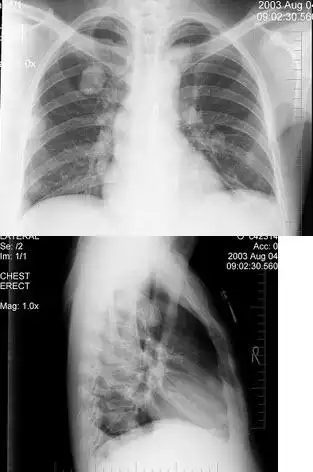

胸片示弥漫性对称性网点状间质性阴影,伴左侧自发性气胸.